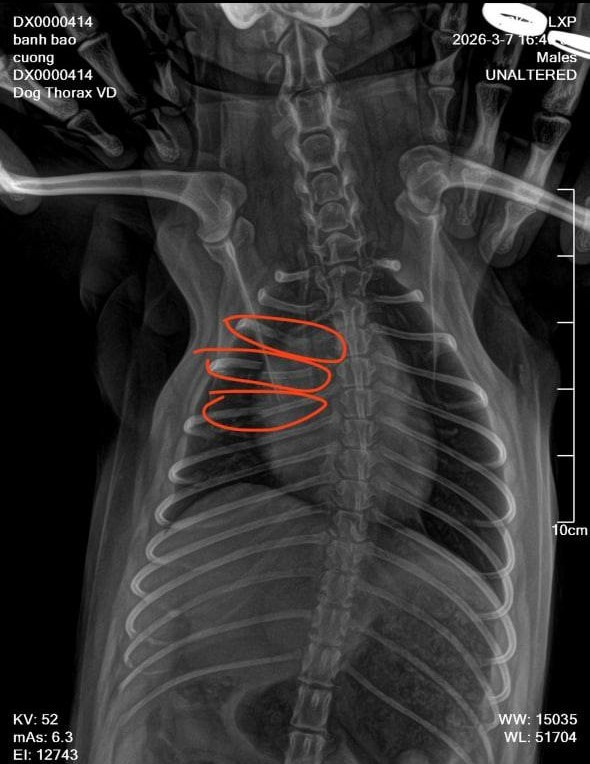

Khoảng 15 phút sau, vợ anh T. quay lại tiệm thì phát hiện chú chó kêu gào vì đau nên lập tức đưa đến phòng khám thú y. Kết quả chụp phim cho thấy chú chó bị gãy ba xương sườn. Do kích thước nhỏ nên bác sĩ cho biết không thể bó bột mà chỉ có thể chờ xương tự liền và theo dõi quá trình hồi phục.